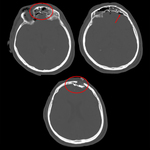

Comminuted nondepressed fracture

From the teaching collection of Demetrios Demetriades; used with permission